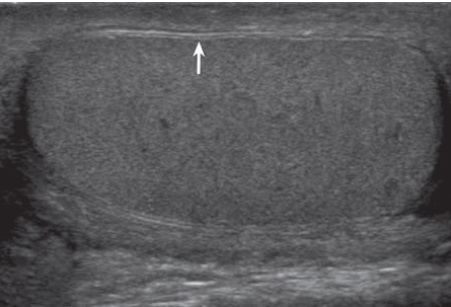

Các dấu hiệu: cấu trúc hồi âm không đồng nhất trong tinh hoàn, bất thường đường viền quanh tinh hoàn, vỡ bao trắng và mất tưới máu trong tinh hoàn là các dấu hiệu đặc trưng của vỡ tinh hoàn

- Rách bao trắng tinh hoàn (Tunica Albuginea): bao trắng bình thường có hình ảnh 2 lớp tăng hồi âm chạy song song với nhau bao quanh tinh hoàn (Hình3). Khi có dấu hiệu mất liên tục của bao trắng có nghĩa là rách bao trắng hay vỡ tinh hoàn (Hình4). Tuy nhiên khi có khối máu tụ lớn ngoài tinh hoàn thì siêu âm hạn chế trong việc phát hiện dấu hiệu rách bao trắng này.

- Cấu trúc hồi âm không đồng nhất của tinh hoàn: cần 1 lực khoảng 50 kg mới có thể làm vỡ bao trắng tinh hoàn[2],[4],[6],[8]. Khi bao này vỡ thì hầu như nhu mô tinh hoàn bên dưới bị tổn thương do đó khi có dấu hiệu cấu trúc hồi âm không đồng nhất của tinh hoàn kèm với đường viền tinh hoàn không đều là có thể chẩn đoán vỡ tinh hoàn. Tuy nhiên với 1 lực nhỏ hơn chưa thể làm vỡ bao trắng nhưng cũng đủ làm đụng dập nhu mô tinh hoàn cho nên dấu hiệu cấu trúc hồi âm không đồng nhất của tinh hoàn một mình nó không đủ để chẩn đoán vỡ tinh hoàn trừ khi đi kèm với dấu hiệu vỡ bao trắng hay đường viền tinh hoàn không đều.

Siêu âm có độ chính xác thấp trong chẩn đoán vỡ tinh hoàn nếu chỉ dựa vào dấu hiệu rách bao trắng với độ nhạy 50% và độ đặc hiệu 76%. Thêm các dấu hiệu như: cấu trúc hồi âm không đồng nhất và bất thường đường viền tinh hoàn đã được báo cáo là nâng độ nhạy và độ đặc hiệu của siêu âm trong chẩn đoán vỡ tinh hoàn lên 100% và 93,5% [2]